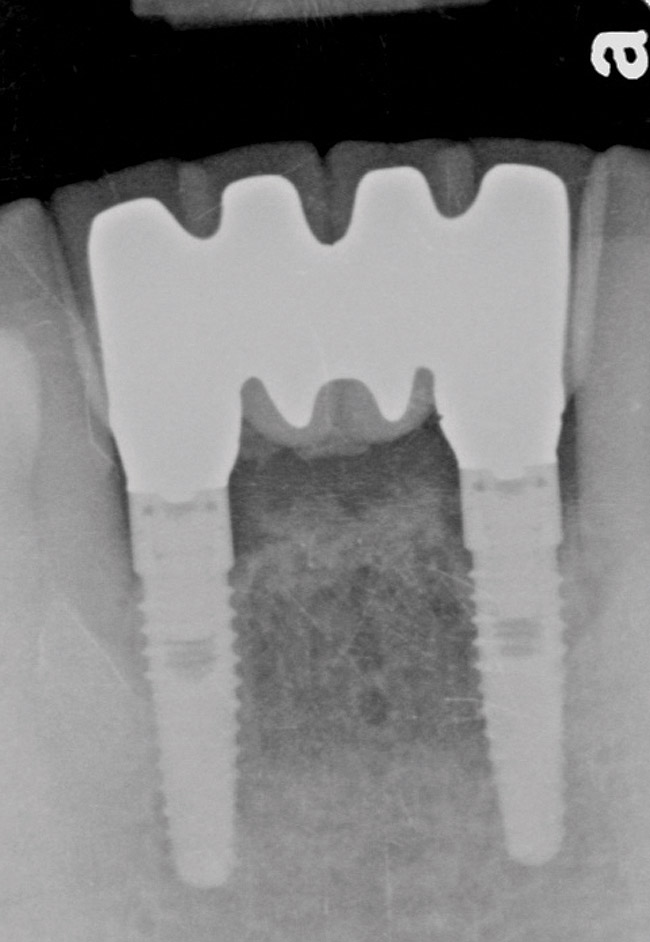

Figure 2  The preoperative radiograph shows healthy cuspids and advanced periodontal disease on the four mandibular incisors.

Figure 2

Figure 12  The 4-year postoperative radiograph.

Figure 12